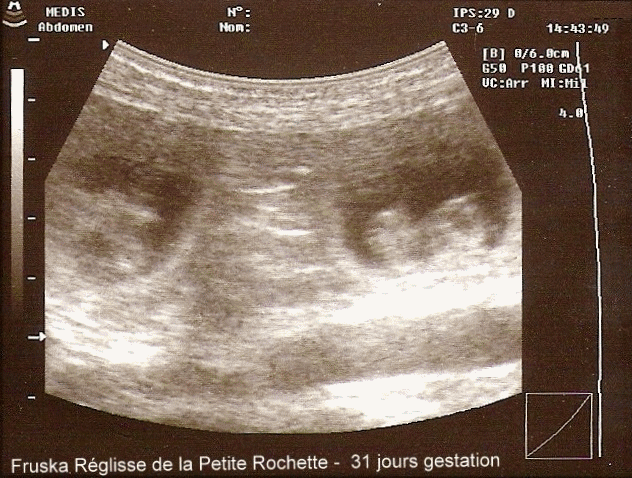

Histoire d'une portée : L'aventure Allemande

L'attente des Petits Pipoux